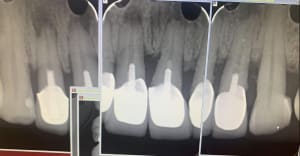

Capture_d_écran_2019-09-05_08.53.43_xrhdot.png